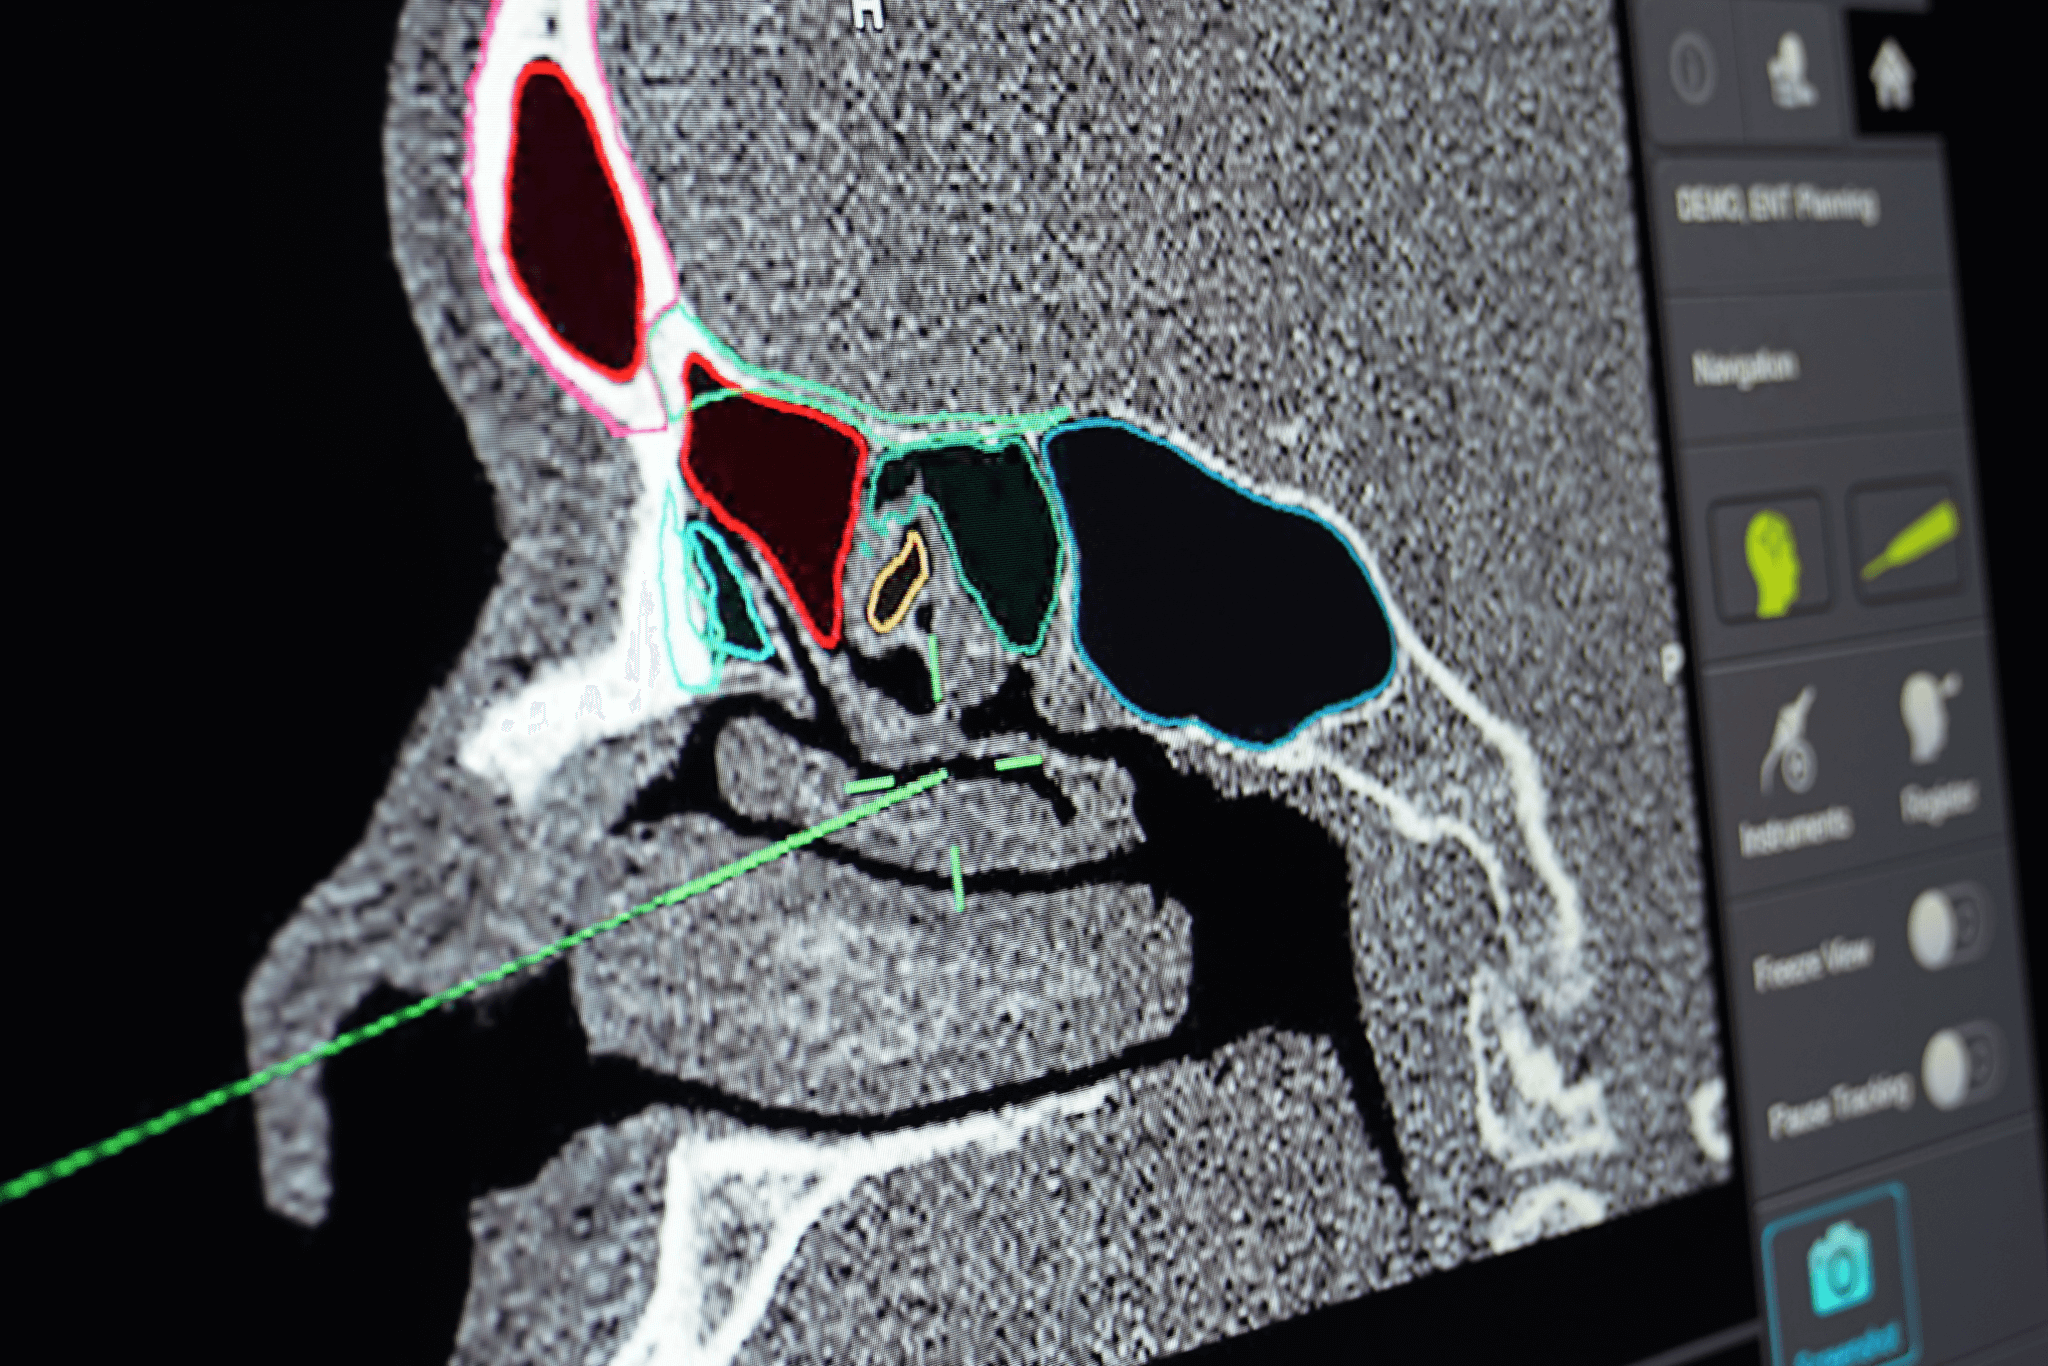

• Intraoperative navigation and its role due to proximity to cranial base and orbit